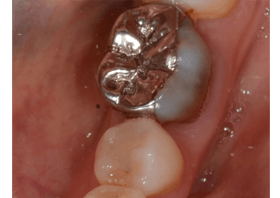

Before

ホワイトニングの後、オールセラミッククラウン、セレックを用いた男性の場合

| 治療内容 | ホワイトニング治療後にオールセラミッククラウンとセレックによる審美治療を行いました。 |